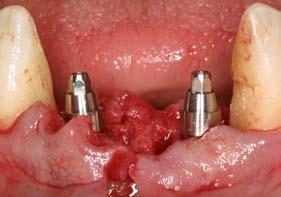

Seguimiento clínico a 25 años de una rehabilitación implantosoportada en una paciente joven con periodontitis de inicio temprano: reporte de caso

Se presenta el caso de una paciente de sexo femenino, de 55 años, que acude a consulta portando una prótesis removible superior anclada a un molar remanente correspondiente a la pieza 17, la cual presenta una marcada pérdida ósea. El resto de las piezas dentales habían sido previamente extraídas debido a enfermedad periodontal. La paciente solicita una alternativa a su prótesis actual, ya que no satisface sus necesidades estéticas ni funcionales.

En la radiografía inicial (Figura 1) se observa la pieza 17 con pérdida ósea significativa, así como una reabsorción ósea homogénea a lo largo de todo el arco superior. En la arcada inferior se aprecia pérdida ósea horizontal generalizada y defectos localizados, como una lesión en cuña en la pieza 46. Ante esta situación, se decide realizar la exodoncia del molar remanente del

arco superior y planificar una rehabilitación implantosoportada para todo el maxilar superior, así como para el extremo distal del tercer cuadrante.

En el arco superior se planifica una rehabilitación cementada por tramos, que en ese contexto representaba la mejor alternativa en términos de estética y estanqueidad, mediante pilares específicos para fresado. Para ello se programan 10 implantes. En una primera fase se realiza la carga inmediata

del sector anterior y la carga definitiva de los implantes mandibulares mediante una prótesis de resina atornillada (Figura 3).

Se realiza la colocación inmediata de implantes en los alveolos postextracción correspondientes a los incisivos laterales, con carga inmediata. Los alveolos de los incisivos centrales se regeneran exclusivamente con PRGF-Endoret. Dada la adecuada estabilidad primaria

obtenida, se opta por la carga inmediata. Durante el acto quirúrgico se colocan los transepiteliales y se toman los registros necesarios, lo que permite instalar una prótesis provisional de carga inmediata pocas horas después (Figuras 15–18).